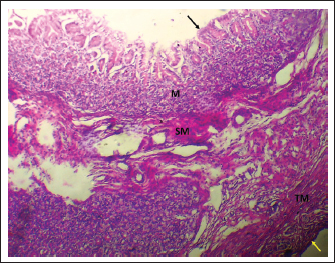

In puppies, the mucosa lining the internal stomach surface varies into a variety of regions depending on the dominant glandular structures, i.e., the cardiac, fundic, and pyloric regions. Microscopically, the gastric wall is made up of four diverse layers or tunics: mucosa, submucosa, muscularis, and serosa, all adding up to the overall structural and functional integrity of the organ (Figs. 1, 4, and 7).

Fig. 1. Shows the four tunics of the cardiac zone in the neonatal dog: Mucosa (M), epithelium (black arrow), submucosa (SM), muscularis (TM), and serosa (red arrow). H&E stain X40.

The cardiac glands were located exclusively near the cardiac orifice. Histologically, they were simple, branched, and tubular, forming shallow, slit-like gastric pits. The stomach wall consisted of the standard layers: a mucosa with simple columnar epithelium, a two-layered muscularis mucosa, a loose connective tissue submucosa, a two-layered muscularis with Auerbach’s plexus, and an outer serosa. In this region, the glands were composed mainly of mucous cells with low columnar shapes and basal nuclei; parietal cells were rare, and chief cells were absent (Figs. 1 and 2). The parietal cells, which had centrally placed nuclei, appeared as spherical or almost spherical bodies. The secretory units of the cardiac glands had an oval or spherical form, and their overall number was lower than that found in other stomach regions (Figs. 2 and 3). This investigation found that, in the cardiac gland area of puppies, the average measurements for epithelial height, lamina propria thickness, and the muscularis mucosa, submucosa, muscularis, and serosa layers were around (15.22 ± 1.12 µm, 125.21 ± 1.15 µm, 21.10 ± 1.44 µm, 101.63 ± 3.11 µm, 200.10 ± 10.45 µm, and 31.12 ± 2.46 µm) in that order (Table 1). For neonatal dogs, the calculated number of glands in this area reached 22.42 ± 1.22, while the mean counts for the cells of parietal and chief about (0.72 ± 0.16; 2.24 ± 0.11), respectively.